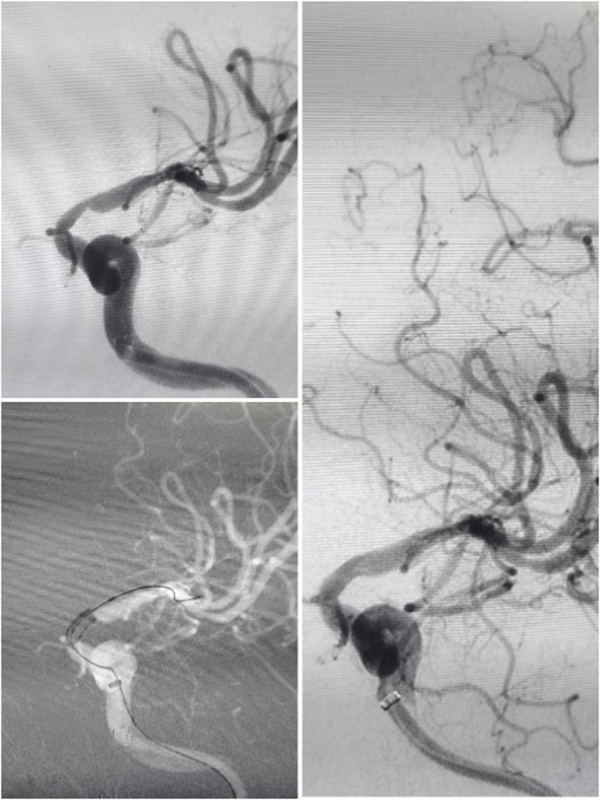

高龄患者前交通不规则动脉瘤

全麻下支架辅助弹簧圈栓塞术

让我印象深刻的是位39岁的年轻男性患者,突发头晕伴右侧肢体麻木无力、言语不利,脑血管造影显示:椎动脉颅内段血管闭塞。患者病情复杂,血管闭塞节段长,而且血管条件差,开通闭塞血管的手术风险也相应增加,但如果选择保守治疗,将来发生严重卒中的风险非常高。

张主任带领团队对患者病情进行了细致分析,制定了详细的手术方案及预案,手术仅耗时40余分钟,夜里23:40,手术圆满结束。

张主任常说“一枝独秀不是春,百花齐放春满园”。他带领神经内科医护团队不断探索,不断解锁“神经密码”,不断穿梭于急诊、门诊和病房之间,挽救了一大批脑血管病患者,守护更多患者的“生命中枢”。